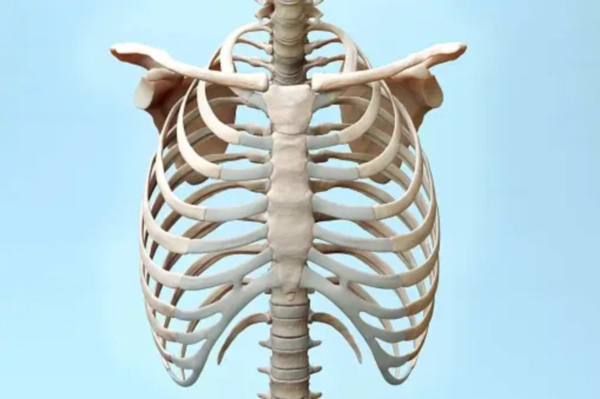

근골격계 문제와 왼쪽 갈비뼈 아래 통증

근골격계 문제는 일상생활에서 흔히 발생할 수 있으며, 왼쪽 갈비뼈 아래 통증의 원인이 될 수 있습니다.

🔹 늑간신경통

늑간신경통은 늑골 사이를 지나는 신경이 자극되어 발생하는 통증으로, 갈비뼈 아래에서 시작되어 가슴과 배 쪽으로 퍼질 수 있습니다. 이러한 통증은 주로 깊게 숨을 쉴 때나 몸을 움직일 때 심해집니다.

🔹 근육 염좌

근육 염좌는 과도한 운동이나 갑작스러운 움직임으로 인해 근육이 손상되어 발생하는 통증으로, 왼쪽 갈비뼈 아래 부위의 통증을 유발할 수 있습니다. 이러한 통증은 주로 근육을 사용할 때 심해지며, 휴식 시에는 완화될 수 있습니다.